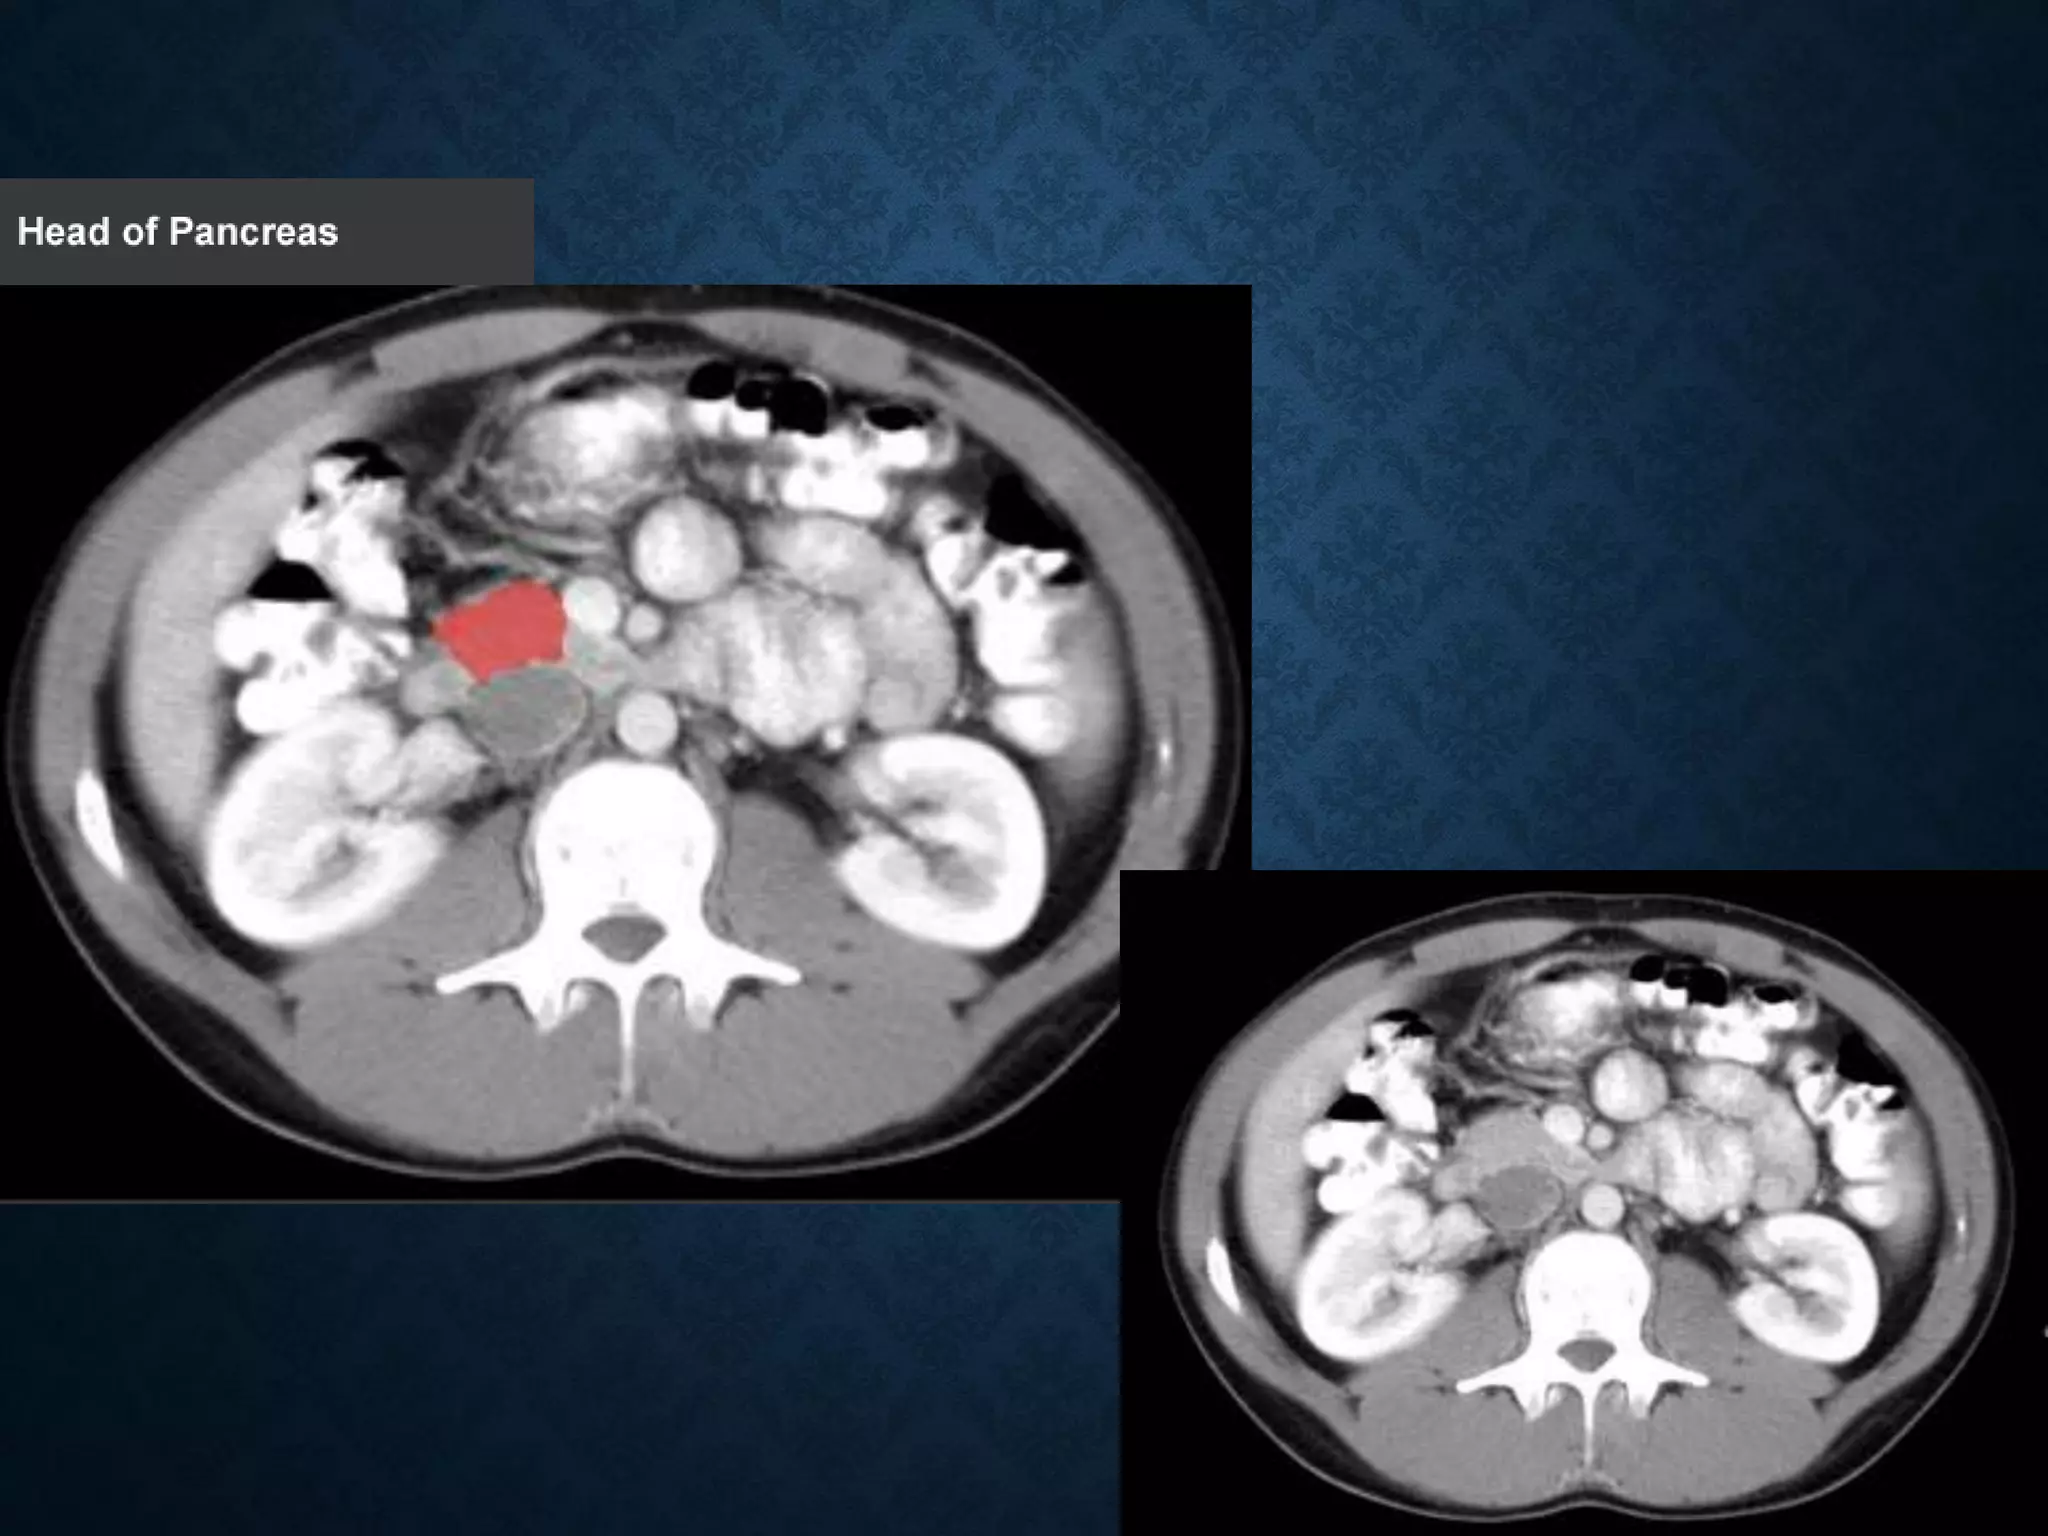

1: Head of pancreas

2: Uncinate process of pancreas

3: Pancreatic notch

4: Body of pancreas

5: Anterior surface of pancreas

6: Inferior surface of pancreas

7: Superior margin of pancreas

8: Anterior margin of pancreas

9: Inferior margin of pancreas

10: Omental tuber

11:Tail of pancreas

12: Duodenum